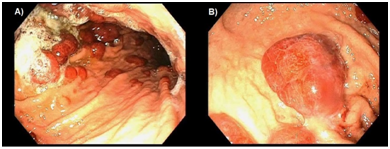

The patient was started on an esomeprazole drip but was hemodynamically stable with initial hemoglobin of 13.2g/dL and did not require blood product transfusion. He did not have further episodes of hematemesis or gastrointestinal bleeding during his hospitalization. The patient was made NPO and gastroenterology was consulted for upper endoscopy which revealed gastritis and medium-sized hemorrhagic nodules in the stomach (Figure 1). Final pathology report of the gastric nodule biopsy showed EBV negative, Germinal Center B-cell type DBCL that was positive for BCL2, BCL6 and CD10; negative for MUM1, CD5 and cyclin-D1; and with Ki67 of 80%. Per PET-CT (Figure 2A), the lymphoma was localized to the stomach (SUV Max 6.5) with FDG avid lymphadenopathy in the in the neck (SUV Max 10.7), chest (SUV Max 10.6), and pelvis (SUV Max 7.9) consistent with stage IV gastric DLBCL. Bone marrow biopsy was performed and returned negative. The patient was also found to have concurrent H. pylori infection.

Figure 1 Endoscopic view of gastric body showing multiple medium-sized nodules in gastric body (A) and fundus (B).